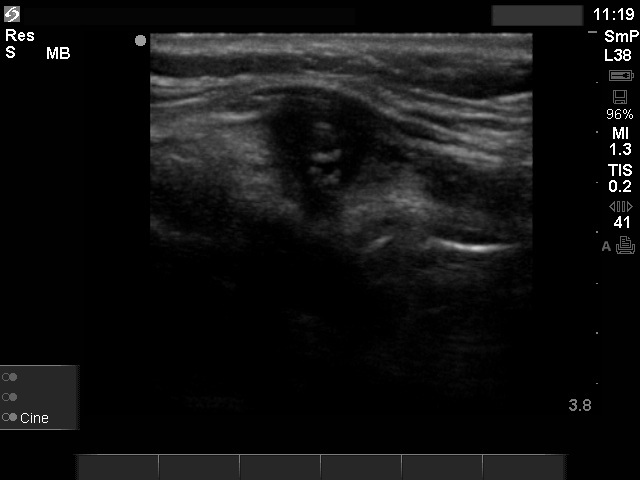

Ultrasonography: there were multiple hypoechogenic lesions containing amorphous hyperechogenic granules in both resected lobes. The lesions were avascular.

Granulation around surgical thread is usually very hard, therefore may suspicious on palpation.

Moreover, the sonographic presentation may also cause fear to an inexperienced investigator not being aware about patient history.